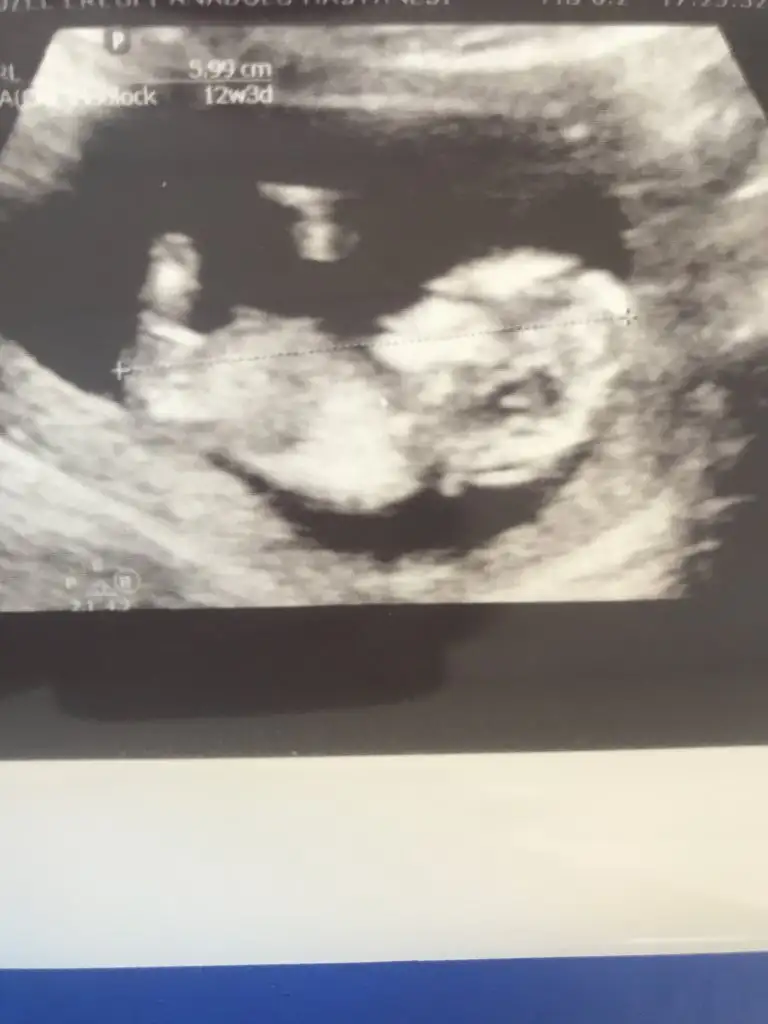

Ikra meyra sizce cinsiyeti nedir? Yardımlarınız için şimdiden teşekkür ederim. Eki Görüntüle 2707799

Çok teşekkür ederimKız gibi görünüyor

Evet erkek gibiBide buna bakın isterseniz.